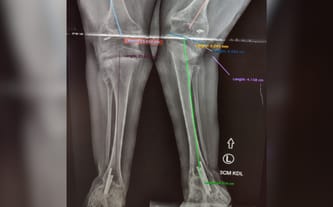

Na chwilę obecną w ciągu roku jej noga skróciła się o 3 cm. Kasia chodzi na zwichniętych biodrach, wykrzywiona kość udowa powoduje rotację kolana do środka, dodatkowo krzywo rosnąca kość piszczelowa pogłębia rotację kolana, powoduje to ogromny ból i dyskomfort, oraz grozi utratą tego, nad czym tak mocno pracowaliśmy – możliwości samodzielnego poruszania się. Konieczna jest pilna operacja.

Mamy już kosztorys z USA i brakuje nam 200 tys. zł – o taką kwotę zwiększamy licznik. Operacja została wyznaczona na 20 maja! Wszystko wskazuje na to, że po tej interwencji chirurgicznej konieczna będzie też operacja zwichniętych bioder. Byliście z Kasią przez ten cały czas, nie zostawiajcie jej i teraz w tak trudnej sytuacji!